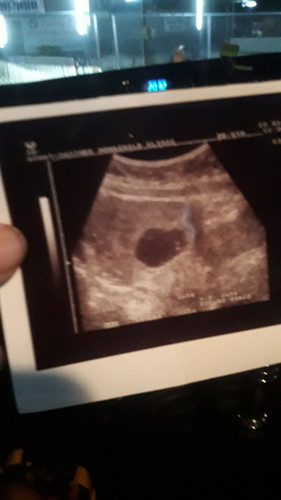

ประจำเดือนเรามาครั้งสุดท้าย16/11/62 วันนี้เราไปหาคุณหมอ เจอแต่ถุงน้ำคร่ำ ไม่เจอตัวน้อง หมอวินิจฉัยว่า ท้องไข่ฝ่อ90% เหลือ10% นัดตรวจอีก2 อาทิตย์ มีคุณแม่ท่านไหนเคยมีประสบการณ์แบบนี้ไหมค่ะ ขอคำแนะนำหน้อยค่ะ